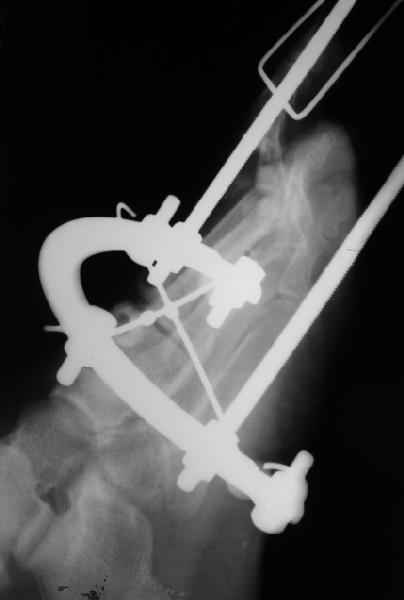

1 передний отдел стопы делается в косой, а не боковой проекции - на боковой все плюсневые кости накладываются друг на друга, и ничего не видно - это же аксиоматично! Я, например, на прямых проекциях не вижу совсем признаков перелома первой и четвертой плюсневой, и сомневаюсь в переломе третьей, боковые же совершенно неинформативны.

Они же наложили дистракционный аппарат (вместо того, чтоб сделать открытое вправление зафиксировать это одной спицой Киршнера), продержали больного две недели в аппарате (ЗАЧЕМ?), а теперь спрашивают , что делать...

Имеем - без малого двухмесячные переломовывихи перeднего отдела стопы , больной в отделении 20 дней, доктор думает, что ему делать:

Та же проблема - по крайней мере на снимке в аппарате (фас) отчетливо видно перелом ее головки.